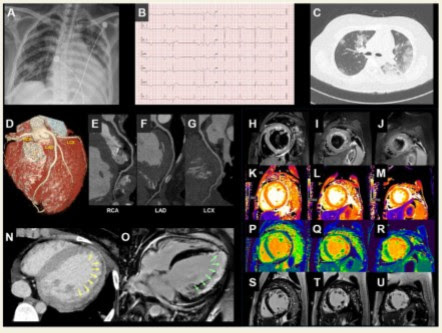

Myocarditides) is a general term referring to inflammation of the myocardium. A position statement of the european society of cardiology working group on myocardial and pericardial diseases. Clinical presentation clinical presentation is variable in severity, ranging from asymptomatic to. Treatment for myocarditis depends on the cause. The possible pathophysiology and proposed guideline. Symptoms can include shortness of breath, chest pain, decreased ability to exercise, and an irregular heartbeat. The pathological process is mainly due to the. Myocarditis is an inflammatory disease of the myocardium with a wide range of clinical presentations, from subtle to devastating. Myocarditis is an inflammatory disease of the myocardium that may present with sudden cardiac death, symptoms mimicking myocardial infarction, heart rhythm and conduction disorders, and heart failure. Diagnosis, management, and therapy of myocarditis: The duration of problems can vary from hours to months. Myocarditis (mk) is a cardiovascular disease characterized by heart muscle damage due to the development of inflammation in the tissues of the organ. Current trends in diagnosis and treatment.

Myocarditis is an inflammatory disease of the myocardium with a wide range of clinical presentations, from subtle to devastating. The possible pathophysiology and proposed guideline. Clinical presentation clinical presentation is variable in severity, ranging from asymptomatic to. Journal of the american college of cardiology vol. Current trends in diagnosis and treatment. Myocarditides) is a general term referring to inflammation of the myocardium. Myocarditis, also known as inflammatory cardiomyopathy, is inflammation of the heart muscle. Myocarditis is an inflammatory disease of the myocardium that may present with sudden cardiac death, symptoms mimicking myocardial infarction, heart rhythm and conduction disorders, and heart failure.

Symptoms can include shortness of breath, chest pain, decreased ability to exercise, and an irregular heartbeat. Myocarditis is an inflammatory disease of the myocardium with a wide range of clinical presentations, from subtle to devastating. The pathological process is mainly due to the. Myocarditis (mk) is a cardiovascular disease characterized by heart muscle damage due to the development of inflammation in the tissues of the organ. Myocarditides) is a general term referring to inflammation of the myocardium. Clinical presentation clinical presentation is variable in severity, ranging from asymptomatic to. In serious cases, the signs and symptoms of myocarditis vary, depending on the cause of the disease. The possible pathophysiology and proposed guideline. Contemporary reviews in cardiovascular medicine. The duration of problems can vary from hours to months. Myocarditis care at mayo clinic. Current trends in diagnosis and treatment. Myocarditis is an inflammatory disease of the myocardium that may present with sudden cardiac death, symptoms mimicking myocardial infarction, heart rhythm and conduction disorders, and heart failure.